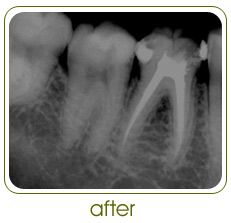

Root Canal Treatment is a procedure in which the nerve

canal of tooth is cleaned, disinfected and filled.

Contrary to popular belief, Root Canal Treatments have

come to be largely painless, predictable and

non-time-consuming procedures.

*All clinical pictures and x-rays on this website are those of cases done at

Doctors Dental Clinic only.